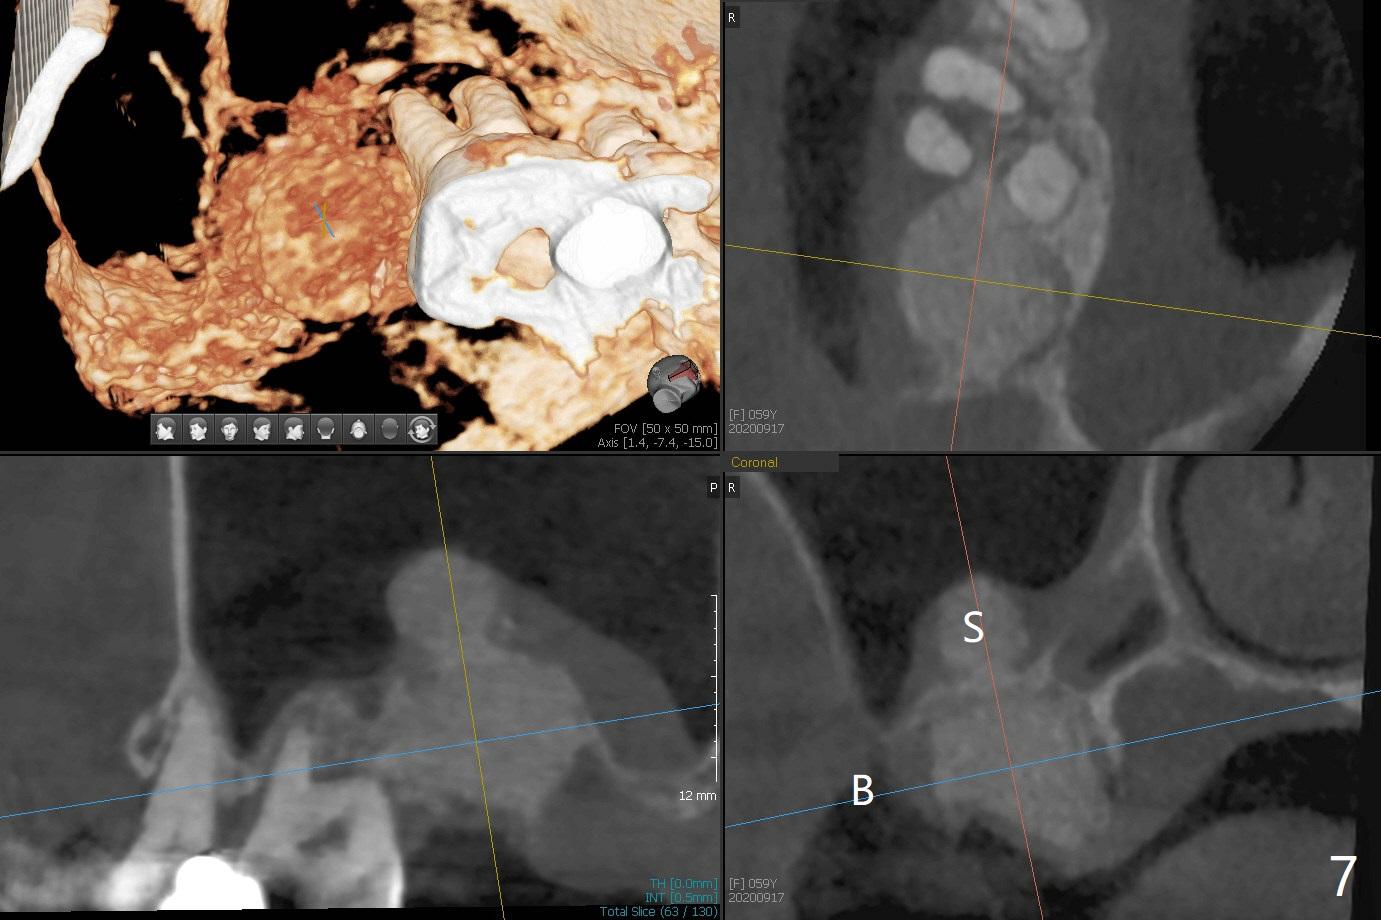

第二磨牙位点保留后,牙周敷料容易脱落,尤其上颌,本文介绍一种方法增加固位。右上七严重牙髓牙周综合征,拔出后使用刮匙除去骨面肉芽组织,颊侧骨板缺失,附着在颊侧粘骨膜上的肉芽组织使用一种叫Stieglitz angled, diamond splinter forceps (德国产,图一,二)撕下来。彻底清除炎性组织必须多次刮治,之间塞入带有灭滴灵(图三:粉剂)和1比50,000肾上腺素局麻药纱布(图四)止血,取出纱布,牙槽窝视野好,继续去除残余的肉芽组织。牙槽窝底部穿孔,用无齿刮匙稍微扩大穿孔后,使用图五下面小的骨粉输送器,将少量骨粉(粘性)送到穿孔处,推入上颌窦(图七:S),之后使用大的骨粉输送器(图五上面),把大量骨粉送到牙槽窝,使用图六上面大的,长的充填器,压实骨粉(图七),骨粉表面放置PRF膜和不可吸收膜(图八),在第一磨牙时安置粘固一个间隙维持器(图九,十),最后铺上牙周敷料(图十一),检查咬合空间,没有干扰。There are sign and symptom of sinusitis 1 week postop; large amount of bone graft retains in the socket by the periodontal dressing and spacer (Fig.12). The sinus membrane (Fig.7 immediate postop) thickens 1 week postop (Fig.13). Augmentin and Medrol Dose Pak are prescribed. 上颌窦炎一周后消失,腭侧牙周敷料丢失,伤口好像正常愈合(图十四)。术后三周牙周敷料由于大量水枪冲洗脱落(图十五)。因为病人需要离城两个月,间隙保持器撤除(图十六),不可吸收膜腭侧稍微外翻 (<),可能有利于术后五周自行脱落。No Deviation SP 下一个病例 位点保留后Xin 导板与张口度 第一磨牙即种 Wei, DDS, PhD, MS 1st edition 09/17/2020, last revision 04/30/2021